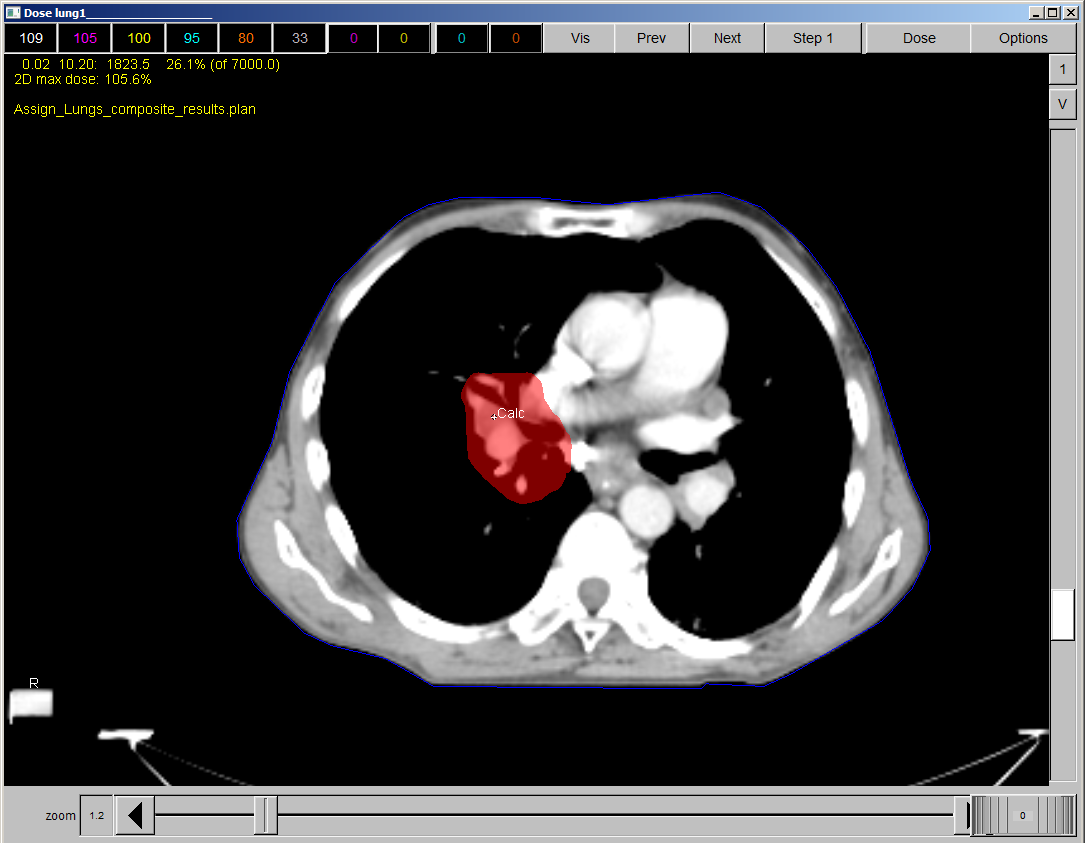

The most common treatment fields for lung cancer are: a) AP/PA only b) 9 fields spaced evenly apart c) AP/PA and off-cord oblique’s; treated subsequently, or together d) A Wedged pair e) Laterals [Note: there was no indication of correct answer]